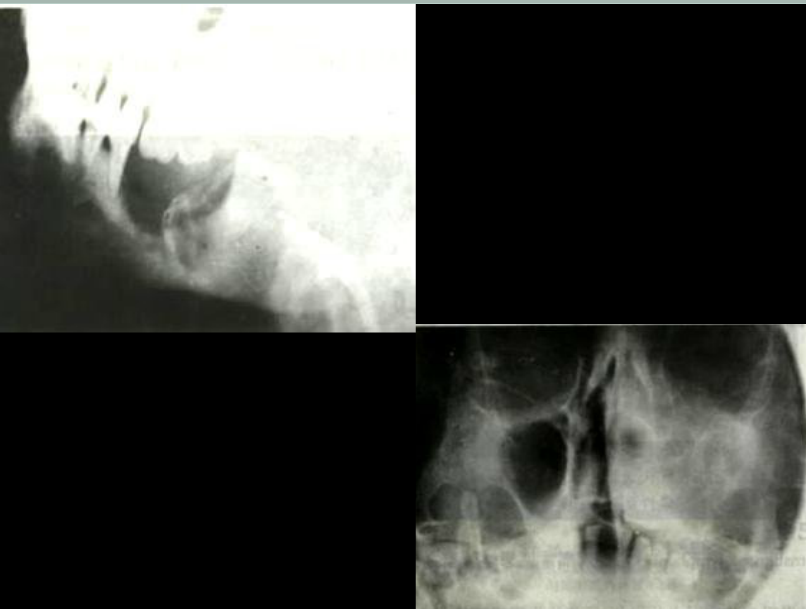

口腔頜面外科 影像技術(shù)